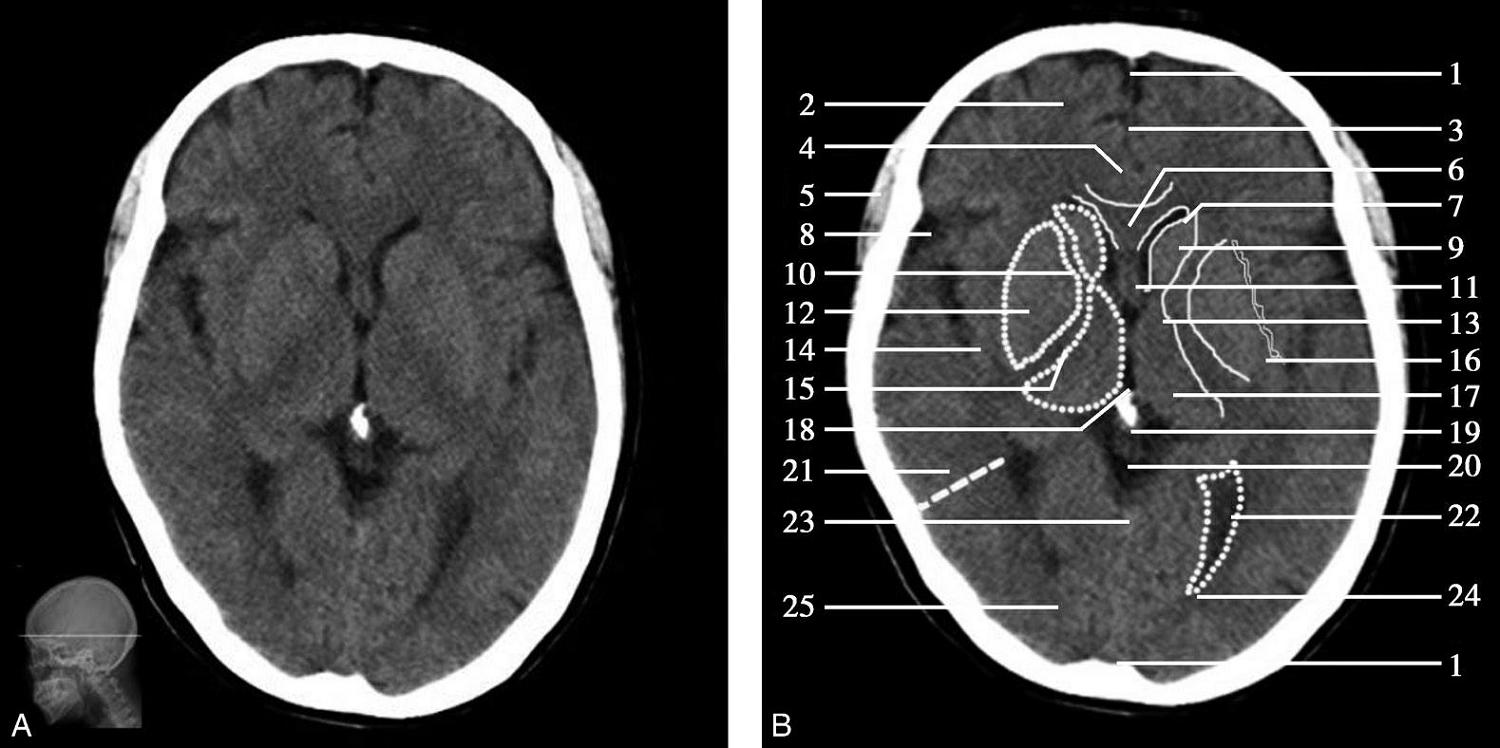

重要结构:丘脑、尾状核头、豆状核、内囊、外囊、侧脑室前角、侧脑室三角区与后角、胼胝体膝、松果体(图1-2-24~图1-2-26)。

图1-2-24 松果体层面

A.横断面;B.横断面标注

1.上矢状窦;2.额叶;3.大脑镰;4.扣带回;5.颞肌;6.胼胝体膝部;7.侧脑室前角;8.外侧裂池;9.尾状核头部;10.内囊前肢;11.透明隔;12.豆状核;13.内囊膝部;14.岛叶;15.内囊后肢;16.外囊;17.丘脑;18.第三脑室;19.松果体(钙化);20.大脑内静脉;21.颞叶;22.侧脑室三角区;23.直窦;24.侧脑室后角;25.枕叶

双侧侧脑室前角呈弯角状,由胼胝体膝、透明隔、穹窿柱及尾状核头围成。侧脑室前角经室间孔与位于中线的第三脑室相通。第三脑室两侧为背侧丘脑,后界为松果体。松果体肿瘤常发生于此(图1-2-27)。尾状核头、背侧丘脑与豆状核之间为内囊,内囊分为前肢、膝部和后肢等三部分。豆状核呈三角形,外侧大部为壳核,内侧部分为苍白球。外囊居壳核的外侧,其外侧依次为屏状核、最外囊、岛叶及外侧裂池。外侧裂池弯曲狭长,内有大脑中动脉走行,外侧有颞叶。松果体后方为大脑大静脉池,大脑大静脉池外侧有侧脑室三角区,其后部伸入枕叶,称后角。侧脑室三角区为后角与下角的移行处,为侧脑室最宽处。由侧脑室三角区向外延伸的虚线可作为横断面颞叶和枕叶的大致分界线。

松果体、苍白球在成人期常出现钙化,属生理性钙化,一般无病理意义。需注意勿误诊为出血灶,尤其是单侧苍白球钙化时(图1-2-28)。

图1-2-28 苍白球生理性钙化